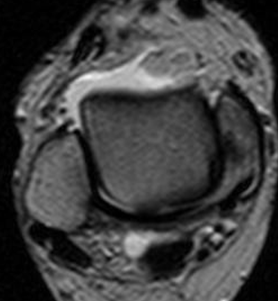

Fig 64 B. Esguince grado III.

RM axial en T2. Ruptura completa del LPAA, con líquido fuera de la articulación.